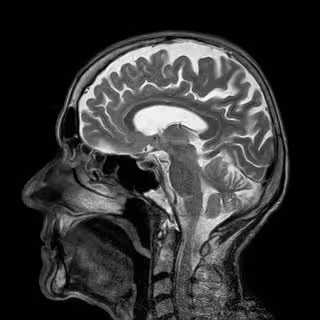

¿Cómo se protege el cerebro ante una dieta rica en grasas?

Cerebro